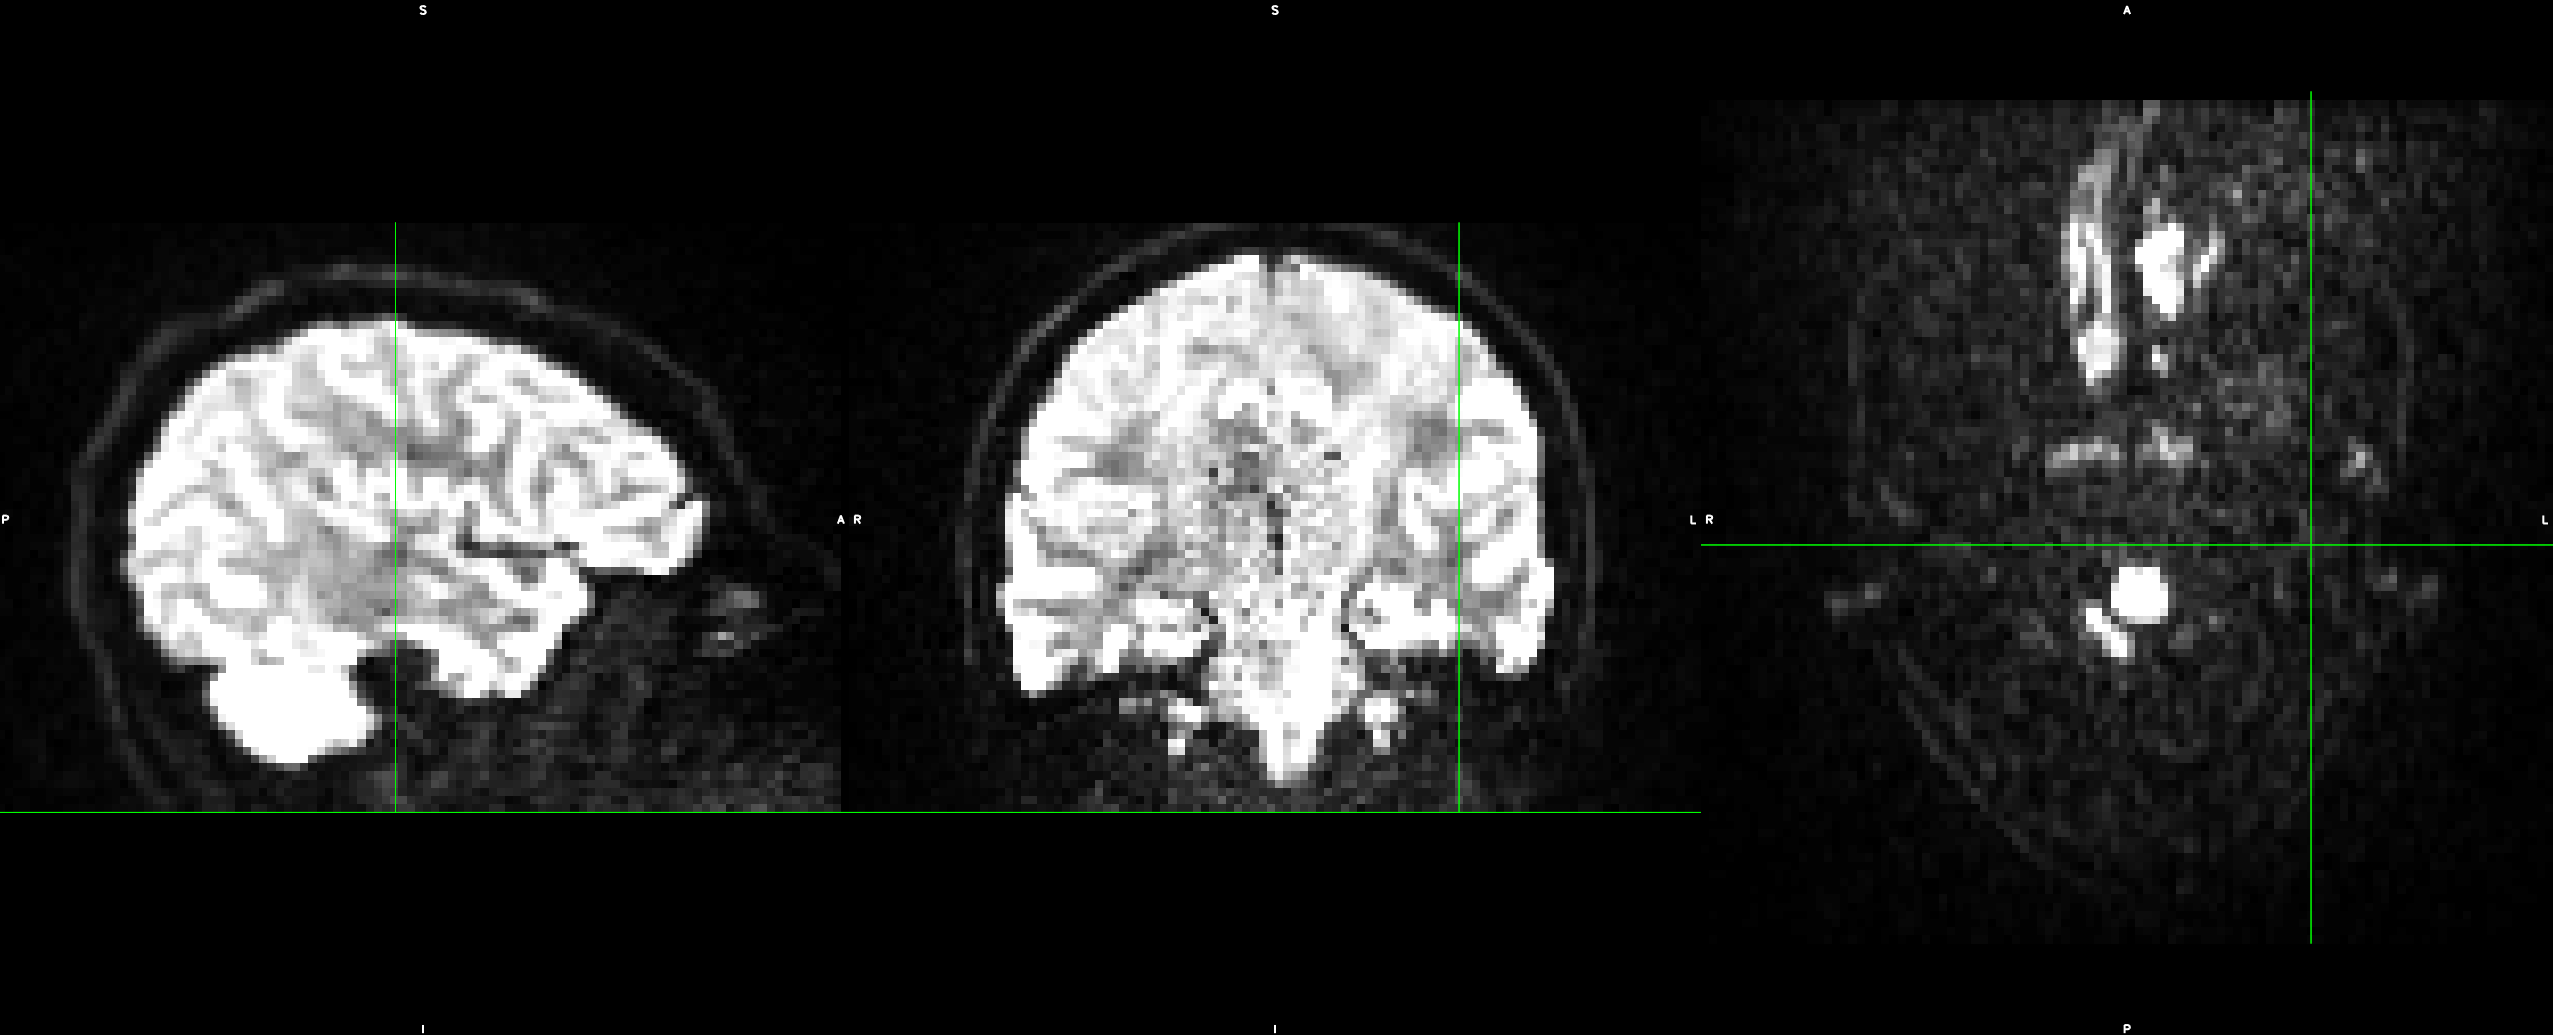

Due to practical constraints on the overall duration of dMRI measurements, the sampling of q-space is usually limited to one or several reference measurements with , as well as one or a few shells with constant , and thus constant . This is illustrated in Figure 1. Such setups focus on the directional dependence of the signal, and typically strive for a uniform distribution of gradient directions on these shells cheng2017single . Our codec assumes dMRI data with such a “shelled” structure, an assumption that is shared by well-established algorithms in the field Andersson2016a .

Traditional PDE-based image compression galic2008image ; 10.1007/978-3-030-56215-1_5 ; jumakulyyev2021lossless ; schmaltz2014understanding performs inpainting in image space, which relies on piecewise smoothness of the image. A key contribution of our current work is to additionally exploit the smoothness in q-space. As it can be seen in Figure 1, dMRI signals that are measured with similar gradient directions are correlated.

From these datasets, we use the five non-diffusion weighted () MRI scans each, as well as 30 diffusion weighted images (, diffusion gradient duration , spacing ). Each image consists of voxels with a resolution of . The data, and the effects of subject motion, are illustrated in Figure 6.